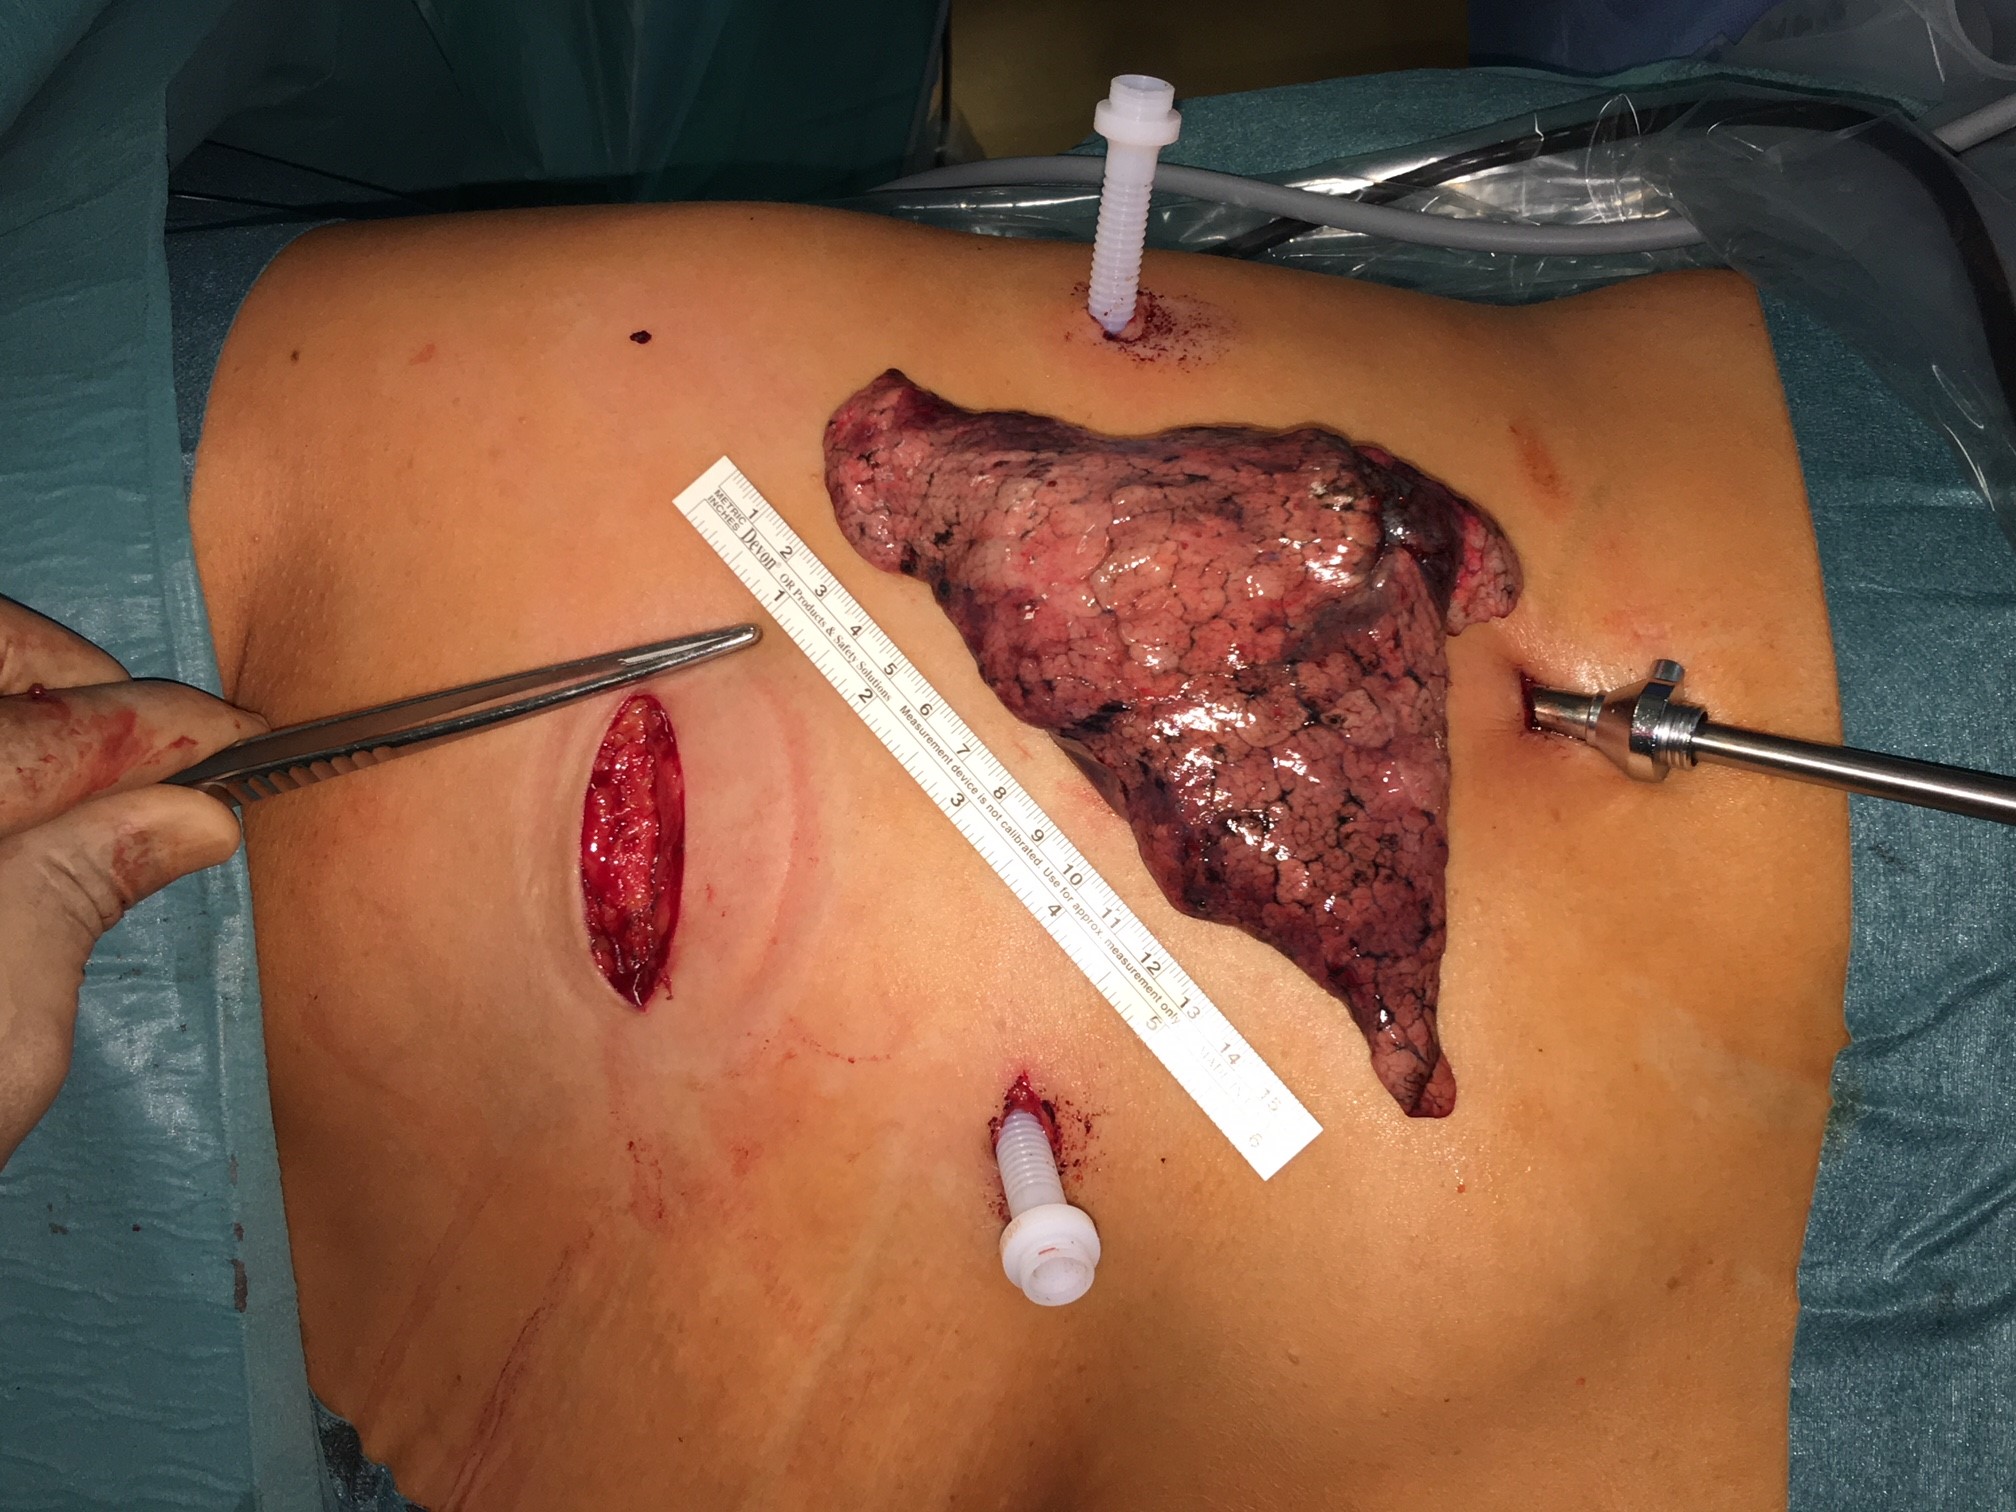

Technisch hoch anspruchsvolle Lungenoperationen können in unserer Klinik auf endoskopische Weise videoassistiert vorgenommen werden (VATS: Video-assistierte Thoraxchirurgie). Die bei konventionellen Lungenoperationen notwendige Eröffnung des Brustkorbs mit einem großen Schnitt und mit Auseinanderspreizen der Rippen entfällt bei der VATS-Lobektomie. Die Patienten erholen sich wegen der sehr viel geringeren Wunde („Operationstrauma“) sehr viel schneller. Auch sind die durch die Operation hervorgerufenen Schmerzen deutlich geringer. Bei einer anatomischen Operation mit Lungenteilentfernung müssen die „Versorgungsleitungen“ durchtrennt werden, dies sind die Blutgefäße und die Luftröhrenäste. Diese Operationsschritte und mehr können endoskopisch vorgenommen und über Video-Übertragung am Monitor mit Vergrößerung durchgeführt werden. Die Technik der VATS–Lobektomie/Lappen-Resektion wird bei Frühstadien des Lungenkrebses erfolgreich eingesetzt wie auch bei einer Vielzahl anderer anatomischer Lungenoperationen (Segmentresektionen).

Lungenmetastasen

Werden neben Lungenkrebs auch Lungenmetastasen diagnostiziert, stellt das die Medizin vor höchste Herausforderungen. Nur wenige Kliniken sind darauf spezialisiert, bei dieser Erkrankung chirurgisch einzugreifen. Durch besondere fachliche Expertise, einen großen Erfahrungsschatz und die technische Ausstattung ist unsere Klinik Ihr Ansprechpartner, wenn es um die chirurgische Therapie von Lungenmetastasen geht.

Laser-Chirurgie bei Lungenmetastasen

In unserer Klinik für Thoraxchirurgie werden zahlreiche Operationen an der Lunge mit dem modernen 1318NM-Diodenlaser durchgeführt. Das neue Gerät wurde speziell für die Lungenchirurgie entwickelt und hat besondere Eigenschaften, die das Schneiden von Lungengewebe ermöglichen: Mit dem Laser ist der Thoraxchirurg in der Lage, bluttrocken und übersichtlich durch das Lungengewebe zu schneiden. Dadurch können Metastasen und Tumoren, die tief im Lungengewebe liegen, onkologisch sicher entfernt werden. Anhand dieses modernen Verfahrens kann der Thoraxchirurg besonders gewebeschonend vorgehen und zahlreiche Lungenmetastasen entfernen, was mit konventionellen Methoden nicht möglich wäre. So kann die Prognose für den Patienten verbessert werden. Die sogenannte Laser-Metastasektomie ist eine etablierte chirurgische Behandlung, die bundesweit nur in großen Thoraxkliniken vorgenommen wird. Unsere Klinik ist die einzige in Ostwestfalen-Lippe, die Laser-Chirurgie bei Operationen der Lunge anbietet.